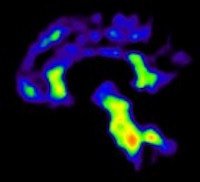

In recent years, both FDG and PiB have become more prominent biomarkers in the diagnosis of several forms of dementia, Ossenkoppele noted. PiB is designed to detect deposits of amyloid plaque in the brain, which have been associated with the onset of Alzheimer's disease. FDG measures metabolic activity of the brain at rest and has been used to distinguish between several forms of dementia.

Researchers then proceeded to the PET scans. First, patients were imaged with PiB for 90 minutes to obtain parametric images of the biomarker binding to potential clusters of amyloid. FDG-PET scans were then conducted 45 to 60 minutes after injection and lasted for 15 minutes. Standardized uptake value (SUV) ratios were calculated throughout the brain.

In the Alzheimer's group, PET with PiB or FDG confirmed a total of 44 (67%) of the 66 cases prior to PET imaging. The second-greatest change was among patients with frontotemporal dementia. PET with PiB or FDG confirmed 11 (61%) of the 18 cases prior to PET.

PiB-PET scans were positive in 40 (61%) of 66 patients with clinical Alzheimer's and in five (28%) of 18 patients with clinical frontotemporal dementia. FDG SUV patterns matched the clinical diagnosis in 58% of patients with Alzheimer's and 33% of patients with clinical frontotemporal dementia, the authors noted.